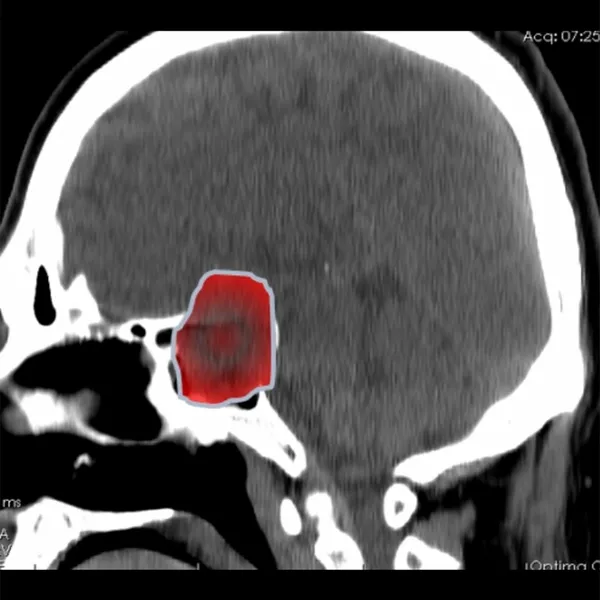

Doktor Ahmet Sinan Tıraş, bu hastalığın basit bir bulantı ve kusma olmadığını ve görme kaybıyla birlikte ciddi bir nörolojik durum olduğunu düşünerek, Nöroloji Doktoru Uzm. Dr. Ceren Kuşakçı'yı bilgilendirdi. Uzm. Dr. Ceren Kuşakçı Tomografi ve MR çekilmesini istedi. Beyin ve Sinir Cerrahisi Doç. Dr. Mehmet Gazi Boyacı ile birlikte MR ve Tomografi sonuçlarını inceleyen hekimler, Hipofiz bezinin altında dev hipofiz adenomu ile karşılaştı. 4 santimetrenin üzerindeki bu kitle; görme sinirlerine baskı yaptığı için görme kaybı oluşan hastaya Göz Hastalıkları ve Sağlığı Doktoru Op. Dr. Mustafa Muhterem Ekim tarafından yapılan tetkikte yüzde 90 görme kaybı olduğu tespit edildi.

Görme sinirlerine baskı giderek arttığı için Beyin ve Sinir Cerrahisi Doç. Dr. Mehmet Gazi Boyacı tarafından acil ameliyat olması gerektiğine karar verildi. Ancak ameliyat için 2 farklı yol olduğunu dile getiren Doç. Dr. Mehmet Gazi Boyacı; kafatasının kesilerek iyileşme süreci uzun olan yöntem yerine, burundan girilerek kitleyi çıkarmanın daha mantıklı ve iyileşme sürecini kısaltan bir ameliyat tekniği olduğunu düşündü.

Kulak-Burun-Boğaz Doktoru Op. Dr. Ersen Koç ile birlikte Transsfenoidal Sinüs Cerrahi(burundan girilerek Sfenoid Sinüs yoluyla yapılan ameliyat) ameliyatı olmasına karar verildi. Ameliyat sonucunda hipofiz bezindeki kitlenin tamamına yakını burnundan çıkarılarak hastanın görme sinirlerindeki baskı ortadan kaldırıldı. Doktorlarımız ve ekibimizin titizlikle yürüttüğü operasyon sonucunda hasta sağlığına kavuştu ve ameliyattan hemen sonra görme oranı yüzde 10'dan yüzde 90'a yükseldi.